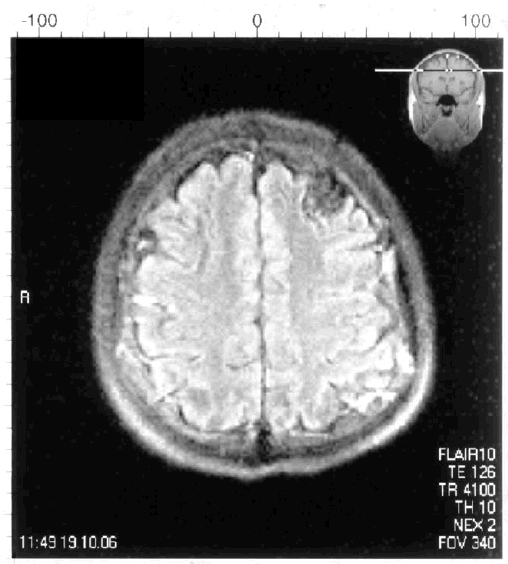

Анализ состояния когнитивных функций, проведенный у 450 пациентов в возрасте старше 65 лет через пять лет после госпитализации по поводу инфаркта головного мозга, выявил клинические проявления сосудистой деменции у 14 % обследованных больных [223]. Сосудистая деменция ассоциировалась с вовлечением в патологический процесс средней мозговой артерии, нейровизуализационными данными (лейкоареоз, множественные ишемические повреждения, кортикальные очаги), наличием сахарного диабета, атриальных фибрилляций, дисфазии, нарушением походки. Такие показатели, как старший возраст и низкий уровень образования, имели независимую корреляционную связь с наличием сосудистой деменции. У обследованных пациентов преобладал церебральный тромбоз (68 %), в 22 % выявлялась внутримозговая геморрагия, у 9 % – субарахноидальное кровоизлияние. Следовательно, развитие сосудистой деменции, которое в большинстве случаев связано с гипоперфузией определенных областей головного мозга, часто происходит в исходе ишемического или геморрагического инсультов. На рис. 6.1 представлена МРТ головного мозга пациента с сосудистой деменцией, развившейся после повторных ишемических инсультов.

Иллюстрация к книге — Деменция. Диагностика и лечение [i_004.jpg]

Рис. 6.1. МРТ головного мозга пациента с сосудистой деменцией